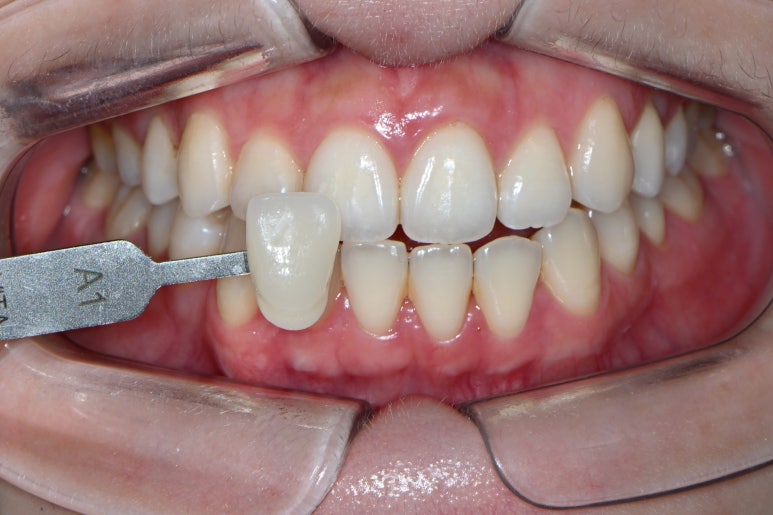

치아미백을 하고난 후 입니다!

VITA Shade guide를 사용했을 때, 치아미백 전에는 A1이랑 비슷했던 색감이 A1을 대면 확실히 더 하얘보이게 바뀐 것을 느끼실 수 있죠...?

전반적으로 노란색을 띄던 감이 많이 사라지고, 이렇게 하얀 톤으로 개선된 것을 보실 수 있을겁니다!!